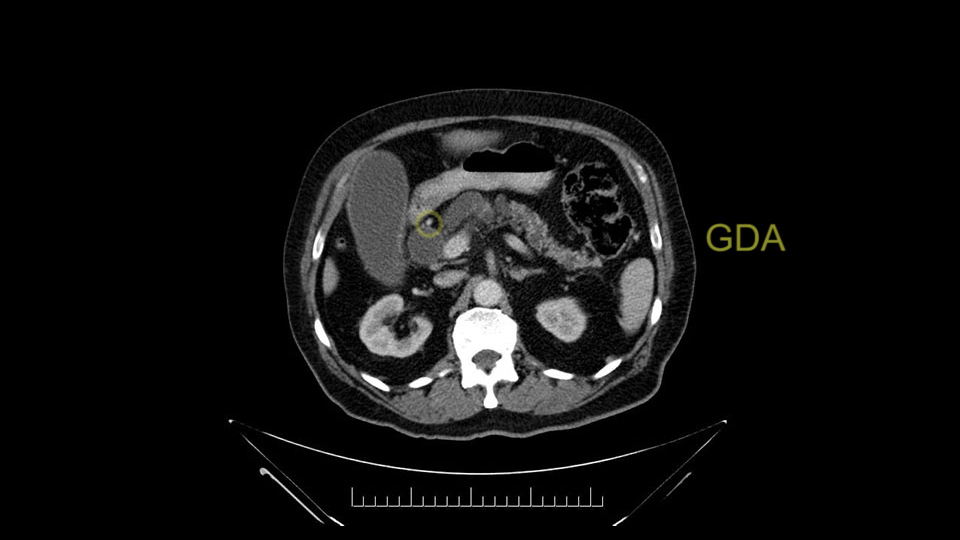

The gastroduodenal artery, a major artery that we have to divide, along with some pancreatoduodenal arteries, may have atherosclerotic changes so they would have to be handled with care, when I attempt what I think would be a pylorus-preserving pancreatoduodenectomy would be the plan. In some cases, I might make an intraoperative change and do a partial antrectomy or a pylorus-resecting Whipple, should the need arise for technical reasons but not because of the size of the tumor.

The other slowing down moment would be the gastroduodenal artery. Confirming that the gastroduodenal artery is not a dominant artery supplying blood to the liver. Liver failure is something which we don’t want due to altered blood supply to the liver or hampered arterial blood supply to the liver. So I would dissect out the hepatic artery, the left and right branches very clearly. Put a bulldog clamp on the gastroduodenal artery, make sure that the perfusion of the liver is excellent on the right and left side, and then divide the gastroduodenal artery. I would avoid using crushing instruments or crushing clamps on the gastroduodenal artery because they have a tendency to shatter in patients who are old with friable vessels so you have to be careful and tackle it with the help of a 5-0 or a 6-0 prolene sutures. In younger patients, I would just apply clips and move on when it comes to dividing the gastroduodenal artery.